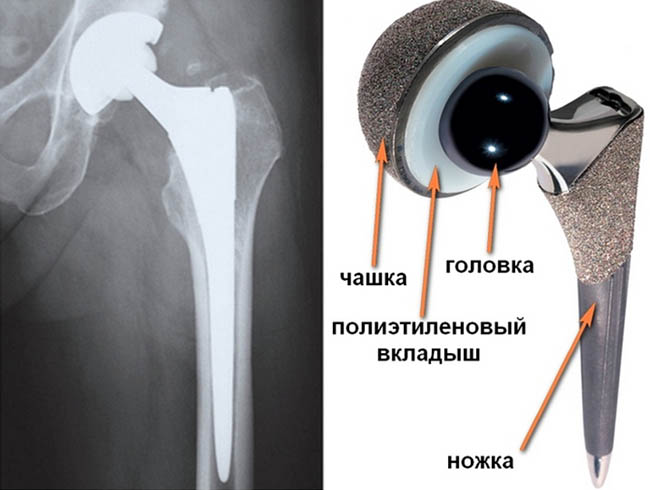

Тотальное и частичное эндопротезирование тазобедренного сустава

Существует два вида эндопротезирования:

-

тотальное;

частичное.

При тотальном заменяют головку и шейку бедренной кости, поверхность вертлужной впадины и суставный хрящ, то есть все элементы сустава и тканей, к которым он крепиться.

При частичном эндопротезировании головка бедра сохраняется. Удаляют только остеофиты (костные наросты) и поврежденный хрящ. При необходимости также очищают и вертлужную впадину, после чего устанавливают протез.

Для его крепления используют:

цементную фиксацию – используют биологический клей, который надежно соединяет кость с элементами сустава;

безцементную – используют конструкции с неровной поверхностью, что со временем обеспечивает срастание с костью;

смешанную – используют оба метода.

Способ фиксации зависит от многих факторов – врач выбирает его индивидуально.